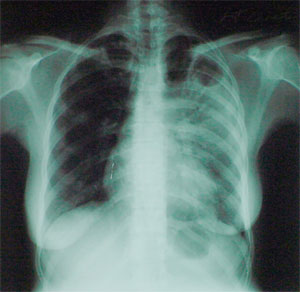

Каждый третий человек на Земле заражен бактерией Mycobacterium tuberculosis — возбудителем туберкулеза. Но из общего числа зараженных заболевает только 5-10%. Выявлен целый ряд факторов, снижающих способность иммунной системы противостоять опасной инфекции (среди них — пожилой возраст, плохое питание, зараженность ВИЧ). Немаловажную роль играют и наследственные факторы. Уже выявлено несколько генов, определенные варианты (аллели) которых связаны с повышенным или, наоборот, пониженным риском развития туберкулеза. Открытие каждого такого гена — важный шаг на пути к победе над заболеванием, уносящим ежегодно от 2 до 3 млн человеческих жизней.

Исследователи сосредоточили свое внимание на гене CD209. Кодируемый этим геном белок DC-SIGN (dendritic cell—specific ICAM-3-grabbing nonintegrin) является рецептором, распознающим специфические углеводы, присутствующие на поверхности многих патогенных микроорганизмов, в том числе M. tuberculosis. Ученым удалось выявить две вариации в промоторе данного гена, частота встречаемости которых значительно выше у здоровых, чем у больных (гуанин в 871-й и аденозин в 336-й позиции, если считать вверх от кодирующей области гена). По-видимому, эти вариации существенно снижают риск заболевания — как обе вместе, так и каждая по отдельности.